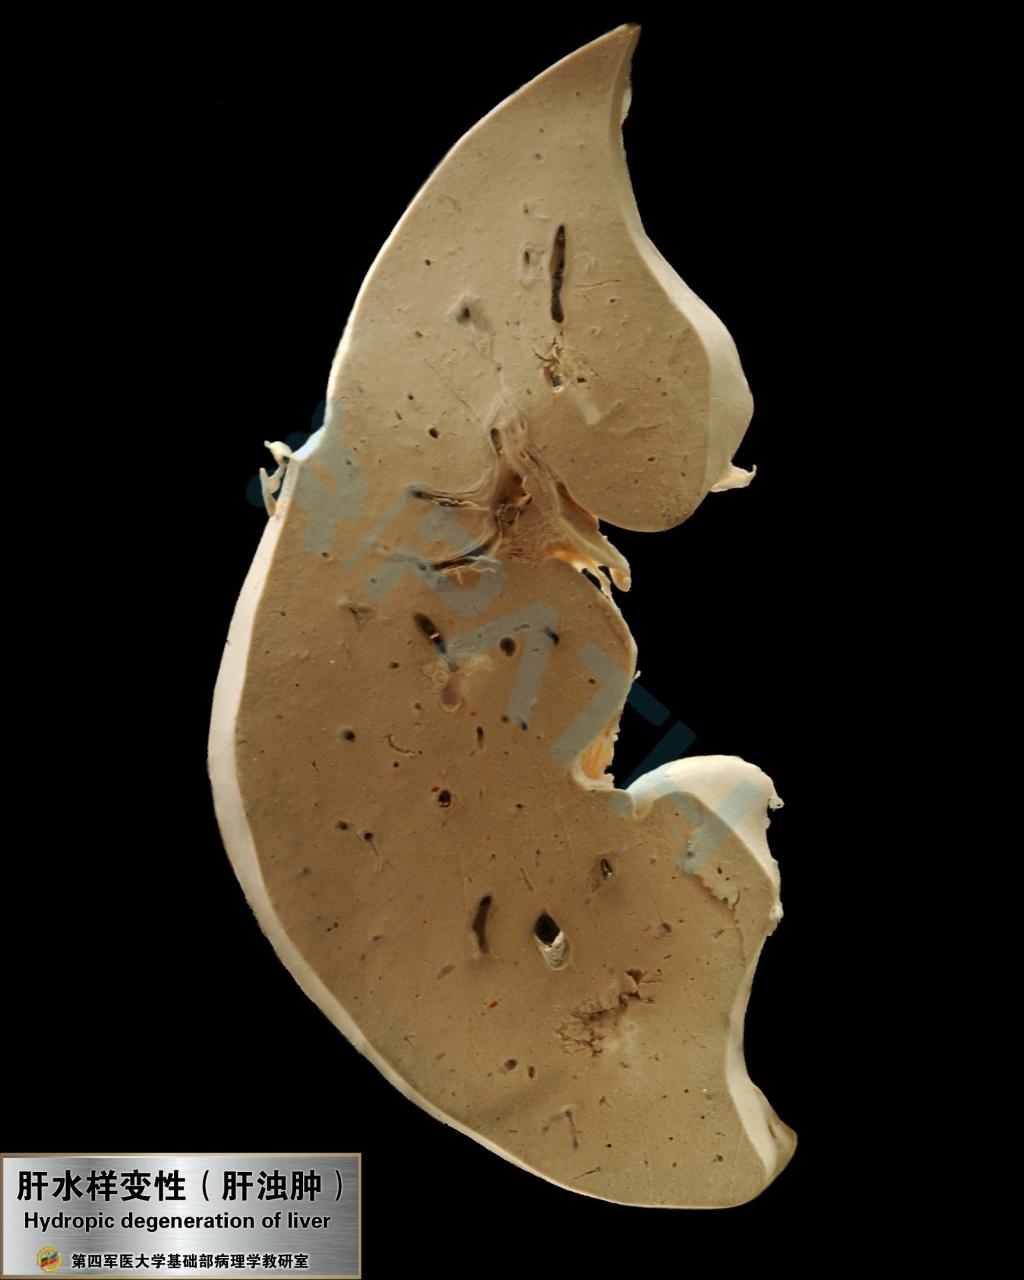

肝水样变性